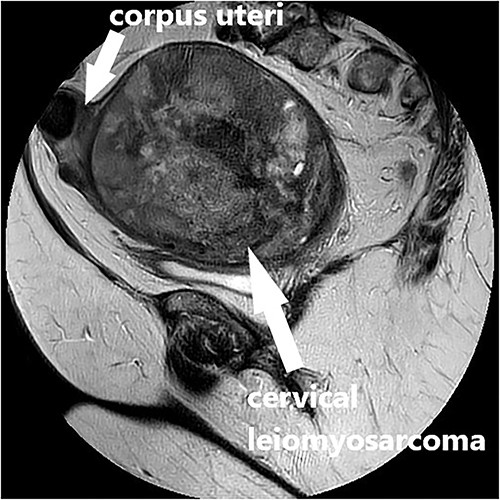

Clinical vaginal examination revealed a circumferentially distended uterine cervix. Vaginal ultrasound scan and magnetic resonance imaging (MRI) showed a strongly vascularized mass that completely involved the whole cervix. The mass measured 118 × 117 × 124 mm and showed irregular echogenicity with signs of diffuse necrosis centrally, suspicious for sarcomatous degeneration (Fig. 1). Positron emission tomography-computed tomography (PET-CT) showed a heterogenous and irregular hypermetabolic uterus, suspected for malignancy (Fig. 2). There were no signs of distant metastases nor lymphadenopathy. PET-CT also showed a distended ureter with hydroureteronephrosis on the right side, suspicious of compression/obstruction of the right ureter (Figs 2–4).

MRI scan, T2-weighted sagittal image of the large vascularized cervical mass in the pelvis with heterogenous and degenerative changes, and corpus uteri on top.